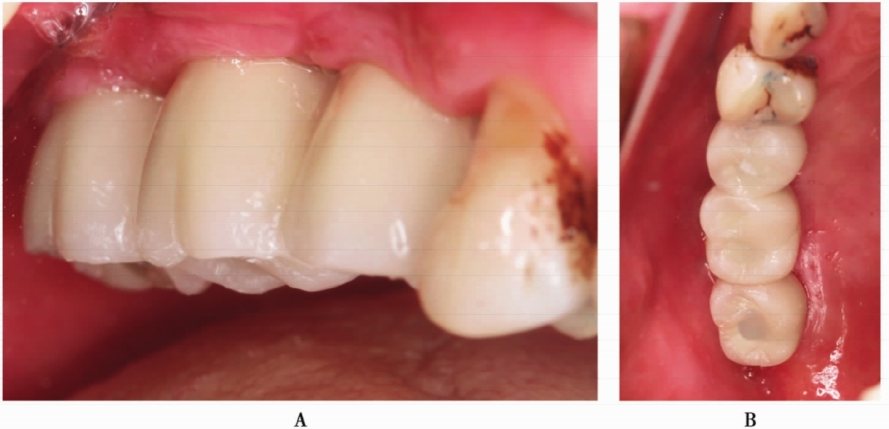

1.单颗牙缺失,同期植入种植体

上颌后牙区第一磨牙是缺失频率较高的牙位(图1A),由于各种原因会导致该位点的牙槽骨高度不足。该病例为47岁男性患者,A6缺失,不吸烟,既往史无特殊,健康状态良好。患者要求种植修复,避免伤及邻牙。

术前CBCT示剩余牙槽骨高度约3mm,近远中距离约10mm,宽度大于8mm,上颌窦内清澈无炎症,上颌窦底黏膜约2mm(图1B,C)。为保证植骨效果,拟进行上颌窦侧壁开窗外提升并同期植入种植体。

图1 A6缺失,CBCT示剩余牙槽骨高度3mmA.口内观;B.矢状面;C.冠状面